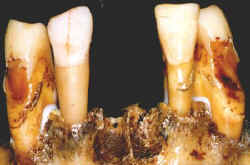

A remodelação alveolar é um processo cronologicamente muito

bem estudado e pode contribuir na determinação da época da perda de dentes ausentes.

Lesões

podem ser encontradas, traduzindo um dado a ser confrontado com exames anteriores ou mesmo

com a história de um abcesso dentário.